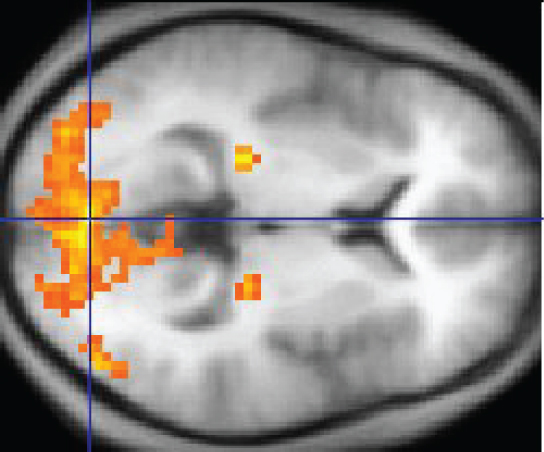

An easy way to see how much of the brain a person uses is to take measurements of brain activity while performing a task. An example of this kind of measurement is functional magnetic resonance imaging (fMRI), which generates a map of the most active areas and can be generated and presented in three dimensions (Figure 14.3.12). This procedure is different from the standard MRI technique because it is measuring changes in the tissue in time with an experimental condition or event.

This MRI image shows a grainy computer readout of a cross section of the brain. The anterior side of the brain, located on the right hand side of the image, has a large area lighting up with yellow, indicating neural stimulation. Two smaller regions at the center of the brain are also yellow. The two small areas are in the same relative location but in opposite hemispheres of the brain.

Figure 14.3.12 – fMRI: This fMRI shows activation of the visual cortex in response to visual stimuli. (credit: “Superborsuk”/Wikimedia Commons)

The underlying assumption is that active nervous tissue will have greater blood flow. By having the subject perform a visual task, activity all over the brain can be measured. Consider this possible experiment: the subject is told to look at a screen with a black dot in the middle (a fixation point). A photograph of a face is projected on the screen away from the center. The subject has to look at the photograph and decipher what it is. The subject has been instructed to push a button if the photograph is of someone they recognize. The photograph might be of a celebrity, so the subject would press the button, or it might be of a random person unknown to the subject, so the subject would not press the button.

In this task, visual sensory areas would be active, integrating areas would be active, motor areas responsible for moving the eyes would be active, and motor areas for pressing the button with a finger would be active. Those areas are distributed all around the brain and the fMRI images would show activity in more than just 10 percent of the brain (some evidence suggests that about 80 percent of the brain is using energy—based on blood flow to the tissue—during well-defined tasks similar to the one suggested above). This task does not even include all of the functions the brain performs. There is no language response, the body is mostly lying still in the MRI machine, and it does not consider the autonomic functions that would be ongoing in the background.